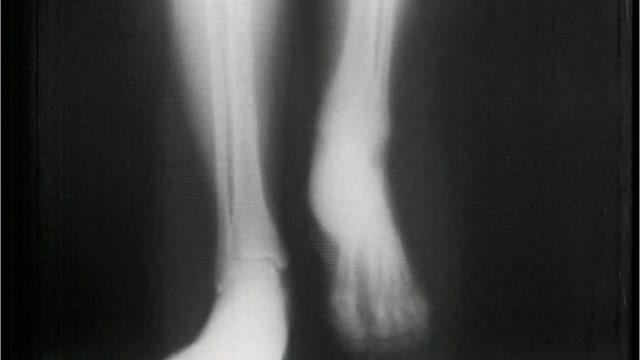

Doctor identifies 'bone death' as long COVID complication